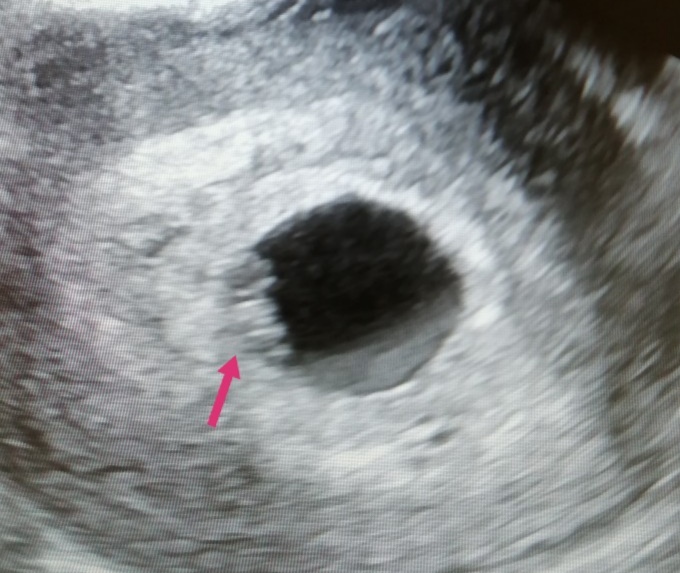

Кто разбирается в этом методе,в интернете написано по месту прикрепления хориона,а как он выглядит то

Тут срок 7+4 трансвагинально

Как я поняла , если справа то девочка

Если слева то мальчик

Смотрят на ранних сроках, у вас уже плацента, а не хорион)))) так что ждите ещё месяц 😉

Читала что до 8 недель спокойно можно посмотреть😅

Просто самое ранние это с 5 недель где только плодное яйцо 😂

У вас уже очень чёткие края, хорион как облачко светлое вокруг яйца.